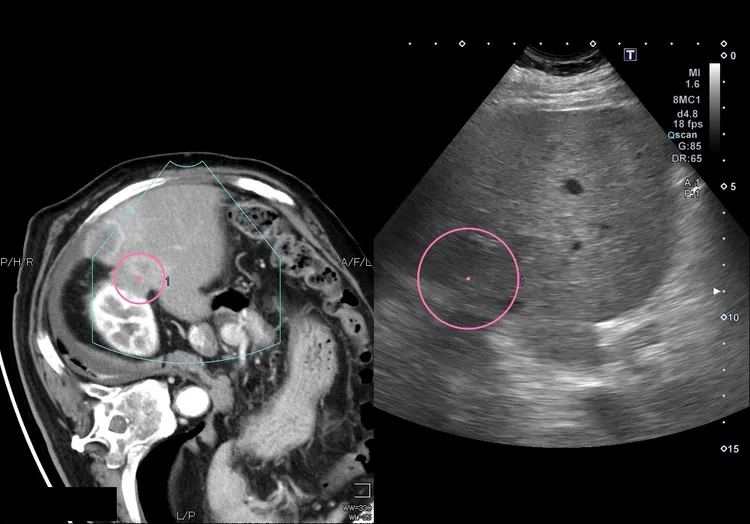

醫療團隊藉由超音波及電腦斷層精準導引定位,成功完成消除肝臟腫瘤目標。亞大附醫提供

然而肝癌並沒有因此而徹底根除,張男今年初定期超音波追蹤時,醫療團隊又發現了一顆1公分大的新生肝內小腫瘤,經電腦斷層確認是復發的肝癌後,決定使用經皮穿肝的「射頻燒灼術(RFA)」消除這顆腫瘤,幾個月後又在定期追蹤時發現三顆復發的肝癌腫瘤,此時病人排除手術治療,同意再度接受「經肝動脈血管栓塞化學療法」治療復發的腫瘤,並接受全身性「免疫藥物」的治療。